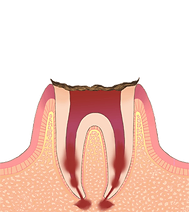

C4【歯根の虫歯】

状態・症状

歯の大部分が虫歯に冒され溶け出してしまった状態。神経が死んでしまっているため、一時的に痛みはなくなりますが、歯根部に膿が溜まると再び痛み出します。

治療方法

ここまでいくと、抜歯が必要になるケースがほとんどです。歯を抜いたあとは、インプラントや入れ歯で咬む機能を回復させます。